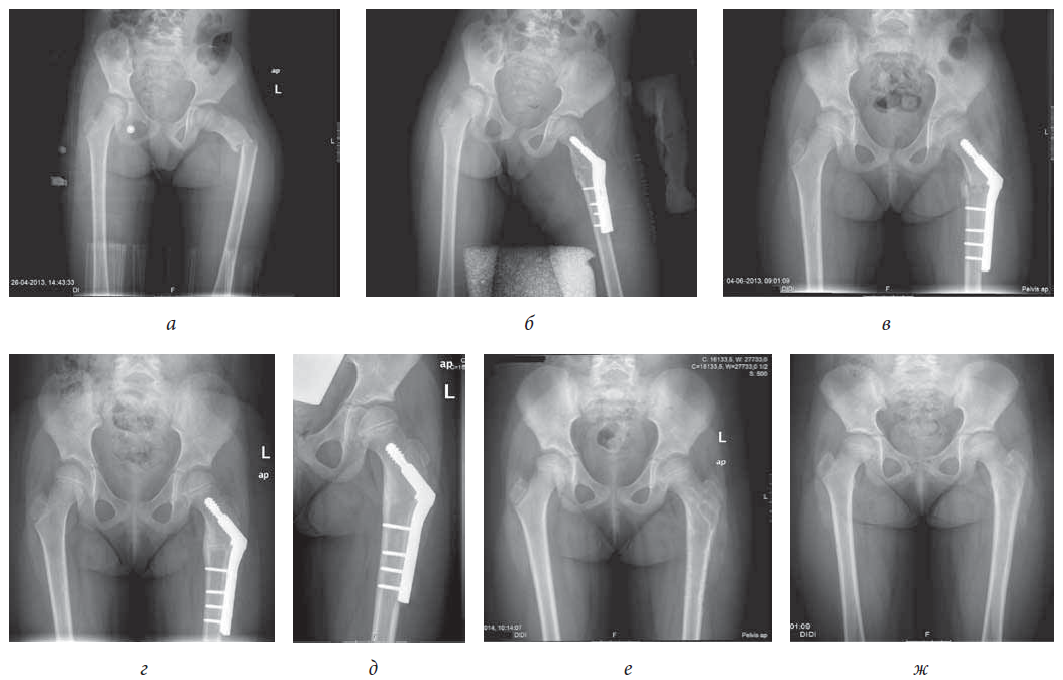

Admission radiographs showed a left proximal femur fracture and a left displaced proximal humeral fracture. The PHF was classified as a Delbet type 4 — extracapsular intertrochanteric fracture (Fig. 1, a).

Fig. 1. Delbet type IV extracapsular displaced intertrochanteric fracture. Radiograph: a — before operation; b — first day after operation; c — one month after operation; d — three months after operation; e — six months after operation; f — one month after the operation of removing the osteosynthesis material; g — fifteen months after the operation of removing the osteosynthesis material

She was put under cutaneous traction and analgesics.

On 2013/04/30 was submitted to open reduction and internal fixation with a pediatric sliding hip screw (SHS). The tip of the SHS did not invaded the physis, being positioned distally to it (Fig. 1, b).

The postoperative period was uneventful. She began the rehabilitation program with increased and progressive weightbearing exercises, after a 4-week-period of non-weightbearing (Fig. 1, c).

The osteosynthesis plate was removed 10 months after surgery (Fig. 1, d, e).

26 Months after the first surgery, radiographs revealed complete bone remodeling and no limb length discrepancy (Fig. 1, f, g). The range of motion (ROM) is painless and full.